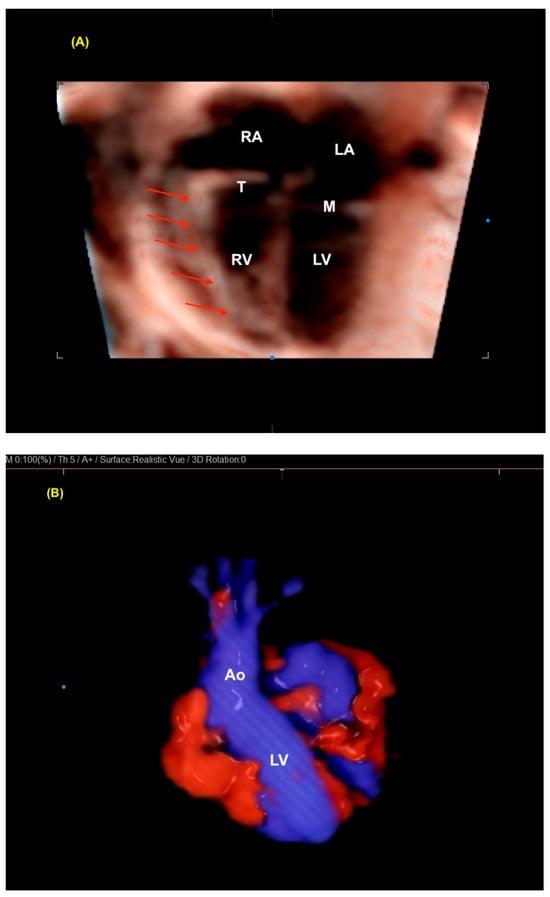

5. Realistic Vue, Crystal Vue, and LumiFlow

Realistic Vue, Crystal Vue, and LumiFlow (Samsung Healthcare, Gangwon, South Korea) provide more detailed and realistic images of the fetus with instant processing, and Crystal Vue improves the visualization of internal and external structures in a single rendered image (Figure 9 and Figure 10 and Video S6). LumiFlow is a post-processing and shading technique used to better assess the fetal micro- and macrovasculature of the fetus. This technology can be added to existing Doppler images, such as color/power, to simulate a 3D pace view of the fetal vasculature. With LumiFlow, the center of the vessel is displayed in a slightly lighter color due to its faster velocity, with a darker border around the vessels where blood velocities are slower (Figure 11) [38,39].

Figure 9.

(A) Realistic Vue surface of a 4-chamber view in a case of tetralogy of Fallot (red arrows: RV hypertrophy). The hypertrophy of the RV is easily seen in this fetus with tetralogy of Fallot because this technology allows the detailed analysis of the cardiac anatomy. (B) Realistic color of the LV outflow tract in a fetus with a normal heart. Note the realistic, high-quality image. LV: left ventricle; RV: right ventricle; RA: right atrium; LA: left atrium; M: mitral valve; T: tricuspid valve; Ao: aorta.